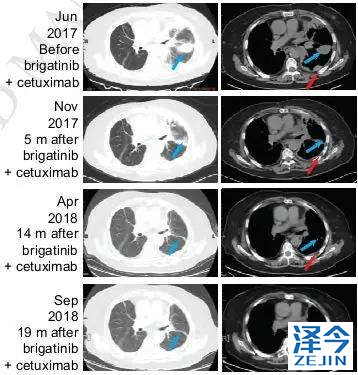

布加替尼联合西妥昔单抗治疗,病情长期稳定控制

患者再次基因检测发现T790M-C797S顺式突变,因此在2017年7月开始联合使用布加替尼(90mg/日)和西妥昔单抗(600mg/月),治疗一个月时,患者的疲劳和呼吸困难明显改善,CA125水平明显下降,直到2018年4月病情一直稳定(PFS为9个月),除了轻度疲劳外无其他的不良反应。虽然在2018年4月患者出现脑转移灶,但在2018年9月,患者的胸部病灶依旧得到很好的控制。

基于上述的理论,国内的研究者首次提出了布加替尼和西妥昔单抗治疗19del /T790M /顺式C797S三突变肺癌的有效临床案例,PFS达到了9个月,疗效显著,毒性也较小。